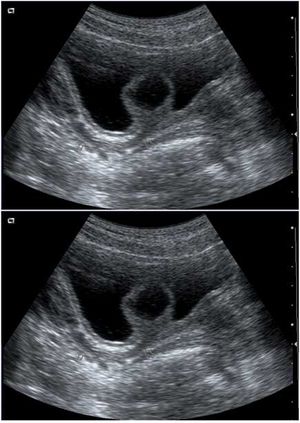

Case History: A 12-year-old girl admitted to our hospital for dysuria. Physical examination was unremarkable. Urianalysis was suggestive of lower urinary tract infection. Urinary ultrasound was indicated.